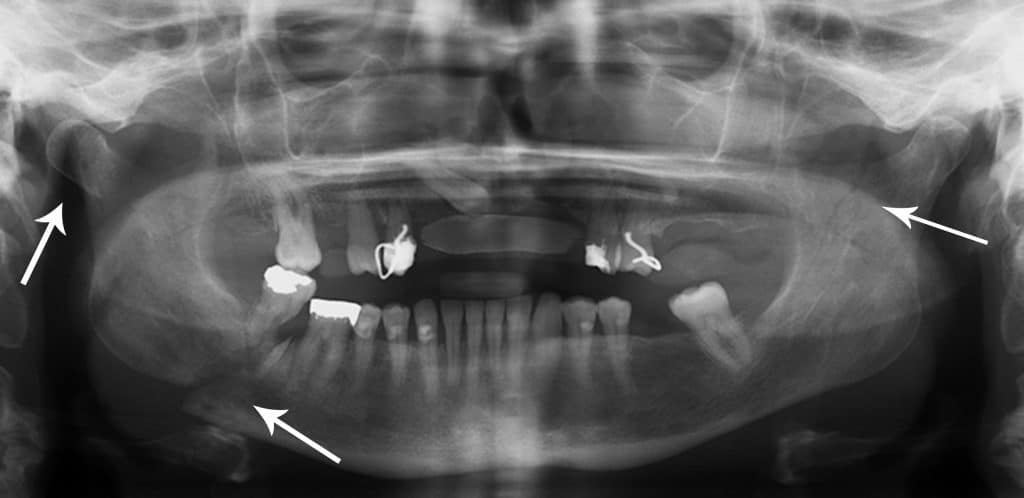

A mandibular fracture rarely occurs in isolation. Much like fractures of the pelvic brim, a fracture on one side is frequently associated with a fracture on the contralateral side.

Therefore, if one fracture is observed, another should be searched for. For example, a fractured neck of the mandible is often observed in conjunction with a fracture of the contralateral mandibular body.

Fig 4 - Multiple mandibular fractures (marked by arrows). This illustrates that fractures of the mandible rarely occur in isolation.

Multiple mandibular fractures (marked by arrows). This illustrates that fractures of the mandible rarely occur in isolation.